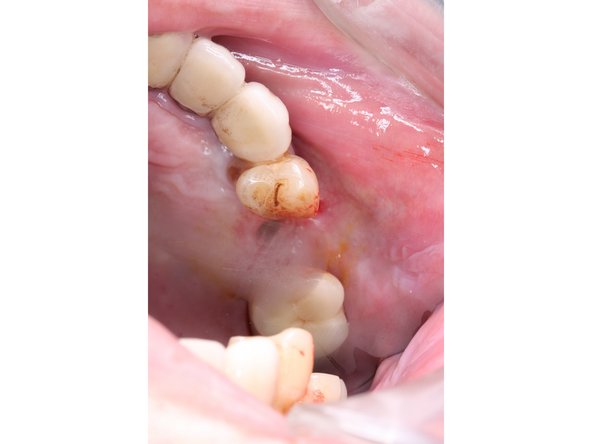

1. 周圍牙齦因堆積食物殘渣而發炎

• 周圍牙齦因堆積食物殘渣而發炎